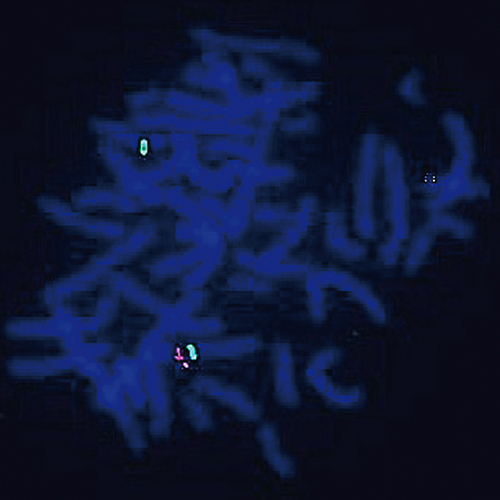

DiGeorge II(10p14) / SE 10 probe hybridized to DiGeorge II patient material showing a deletion of the DGSII region at 10p14 (1R2G). Image kindly provided by Azzedine Aboura, Hôpital Robert Debré Paris.

DiGeorge and VCFS present many clinical problems and are frequently associated with deletions within 22q11.2, but a number of cases have no detectable molecular defect of this region. A number of single case reports with deletions of 10p suggest genetic heterogeneity of DiGeorge syndrome. FISH analysis demonstrates that these patients have overlapping deletions at the 10p13/10p14 boundary. The shortest region of deletion overlap (SRO) has been identified in a 1 cM interval including makers D10S547 and D10S585. The DiGeorge II region probe is optimized to detect copy numbers of the DGSII at 10p14. The chromosome 10 satellite enumeration (SE 10) FISH probe at D10Z1 is included to facilitate chromosome identification.